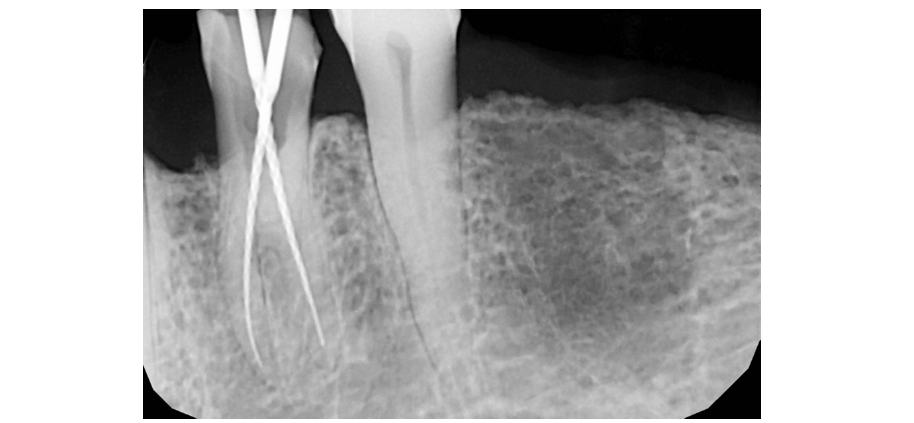

Adequate anaesthesia was achieved with inferior alveolar nerve block. Since the senior citizen had severe gag reflexes the procedure could not be done under rubber dam isolation. The existing cavity preparation was modified, and access cavity was made with round bur; the pulp chamber was entered, and root canal orifices were identified. IOPAR was taken after the initial filing with size 15K-File (Mani, Tochigi, Japan) and found the tooth to have 2 separate roots with 2 different canals of different entry and exit (Figure 2). Working length in each canal was found to be 21 mm. The cleaning and shaping were completed till 6% 25 Hero Shaper files (Micro Mega, Becacon, France). Obturation was done with 6% 25 Master Cone with AH 26 (Dentsply, Germany) as a sealant followed by temporary dressing with Cavit G (3M ESPE, Germany) and postoperative radiograph was taken (Figure 3). Tooth were relieved from occlusion in the functional cusps. The patient was recalled after 5 days for initial review and found to be asymptomatic.

Figure 2:Intra-operative working-length radiograph showing mandibular left first premolar (tooth #34) with a unique radicular anatomy with 2 roots having 2 distinct canals and separate exits.